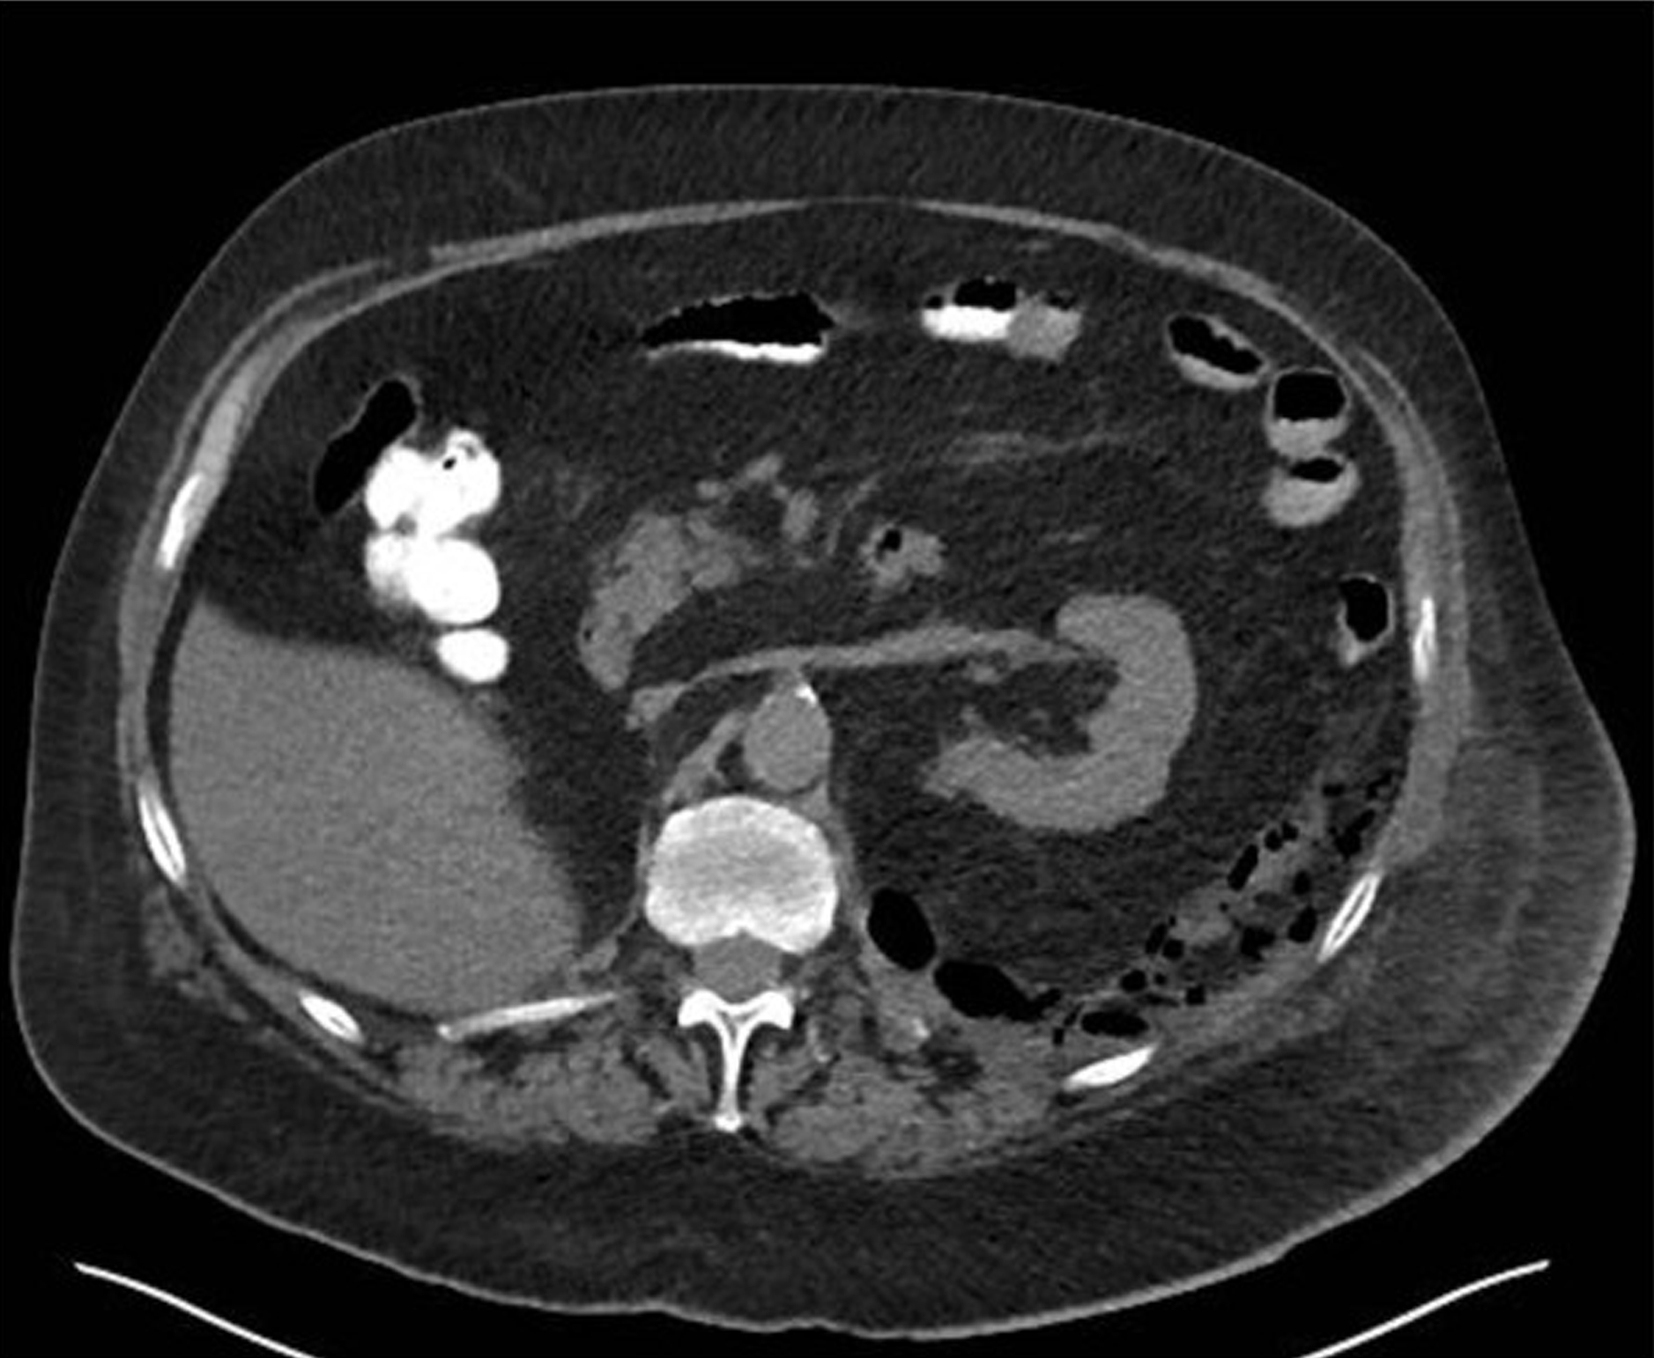

Abdominal CT has become the standard of care for diagnosing diverticulitis. A CT without contrast can identify the presence of diverticular disease. CT with intravenous (IV) contrast is commonly used to assess for diverticulitis. However, CT with both IV and enteric (either oral or rectal) contrast is the ideal method to assess for diverticulitis and any associated complications, with 98% sensitivity and 99% specificity. CT findings may include colonic wall thickening, pericolonic fat stranding, localized perforation (also known as micro-perforation), abscesses, as well as free air or fluid ( Figs. 81.1–81.3 ). While generally outside the scope of ED practice, the Hinchey staging system can be used to stratify diverticulitis based on the level of abscess formation or perforation ( Box 81.4 ).

Uncomplicated diverticulitis (arrow) showing multiple air-filled structures lining the edge of the left colon (diverticuli), and hazy outer border of bowel segment (fat stranding) indicative of inflammation.

Computed Tomography Imaging Demonstrating Diverticulitis With Abscess Formation.

From Sartelli M, Moore FA, et al. A proposal for a CT driven classification of left colon acute diverticulitis. World J. Emerg. Surg . 2015;10(3):1–11, Fig. 4.